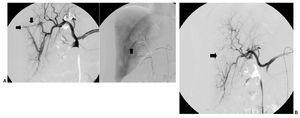

Once lesiones fueron roturas arteriales con formación de pseudoaneurisma de una arteria musculoesquelética (fig. 1) y 9 fueron lesiones en una arteria visceral (fig. 2), 4 de las cuales fueron lesiones de la arteria gastroduodenal (fig. 3), tres secundarias a complicaciones de una duodenopancreatectomía cefálica y otra a una punción directa con un catéter de drenaje 10 french de un absceso secundario a una colecistectomía.

Fig. 1. (A) (caso 13) Arteriografía selectiva de arteria glútea inferior izquierda que pone de manifiesto la rotura arterial y el punto de sangrado activo (flecha). (B) Arteriografía selectiva de glútea inferior e imagen simple sin sustracción que muestran el molde de Onyx cerrando selectivamente el punto sangrante, permaneciendo permeables el resto de ramas arteriales (flecha).